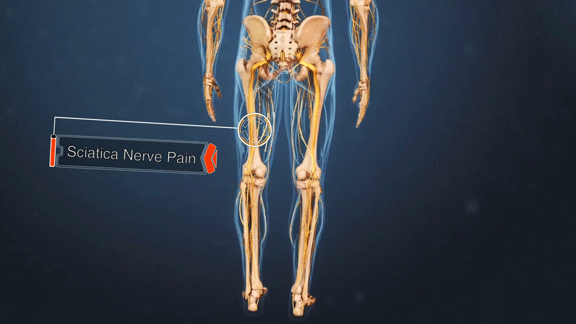

मानवी शरीरातील सर्वात लांब आणि महत्त्वाच्या मानल्या जाणाऱ्या नसांपैकी एक म्हणजे सायटिक नस (sciatic nerve). ही नस कंबरेपासून सुरू होऊन दोन्ही पायांच्या जवळपास घोट्यापर्यंत जाते. कुठल्याही कारणाने या नसेला इजा झाली तर कंबर, पाय, पार्श्वभाग अशा ठिकाणी असह्य वेदना होणं, क्वचित प्रसंगी पायातील शक्ती कमी झाल्यासारखं वाटणं, पायांना मुंग्या येणं, असा त्रास सुरू होतो. हा विकार म्हणजे सायटिका.